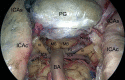

Endoscopic endonasal cadaveric image: After the opening of the bony surfaces over the sellar, clival area and carotid protuberances the neurovascular structures of the left cavernous sinus have been exposed. ICAc: paraclival segment of the internal carotid artery; ICAs: parasellar segment of the internal carotid artery; FL foramen lacerum; PG: pituitary gland; C: clivus; GG: Gasser’s ganglion; VI: abducent nerve; V1: first branch of trigeminal nerve; V2: second branch of trigeminal nerve; V3: third branch of trigeminal nerve; SOF: superior orbital fissure.

Figure 6:

Endoscopic endonasal view of the superior third of the retroclival area; exposure of the neurovascular structures, after bone removal. ICAs: parasellar segment of the internal carotid artery; ICAc: paraclival segment of the internal carotid artery; III: third oculomotor nerve; SCA: superior serebellar artery; PCoA: posterior communicating artery; P1: pre-comunicating tract of the posterior cerebral artery; MB: mammilary body; PG: pituitary gland; BA: basilar artery.